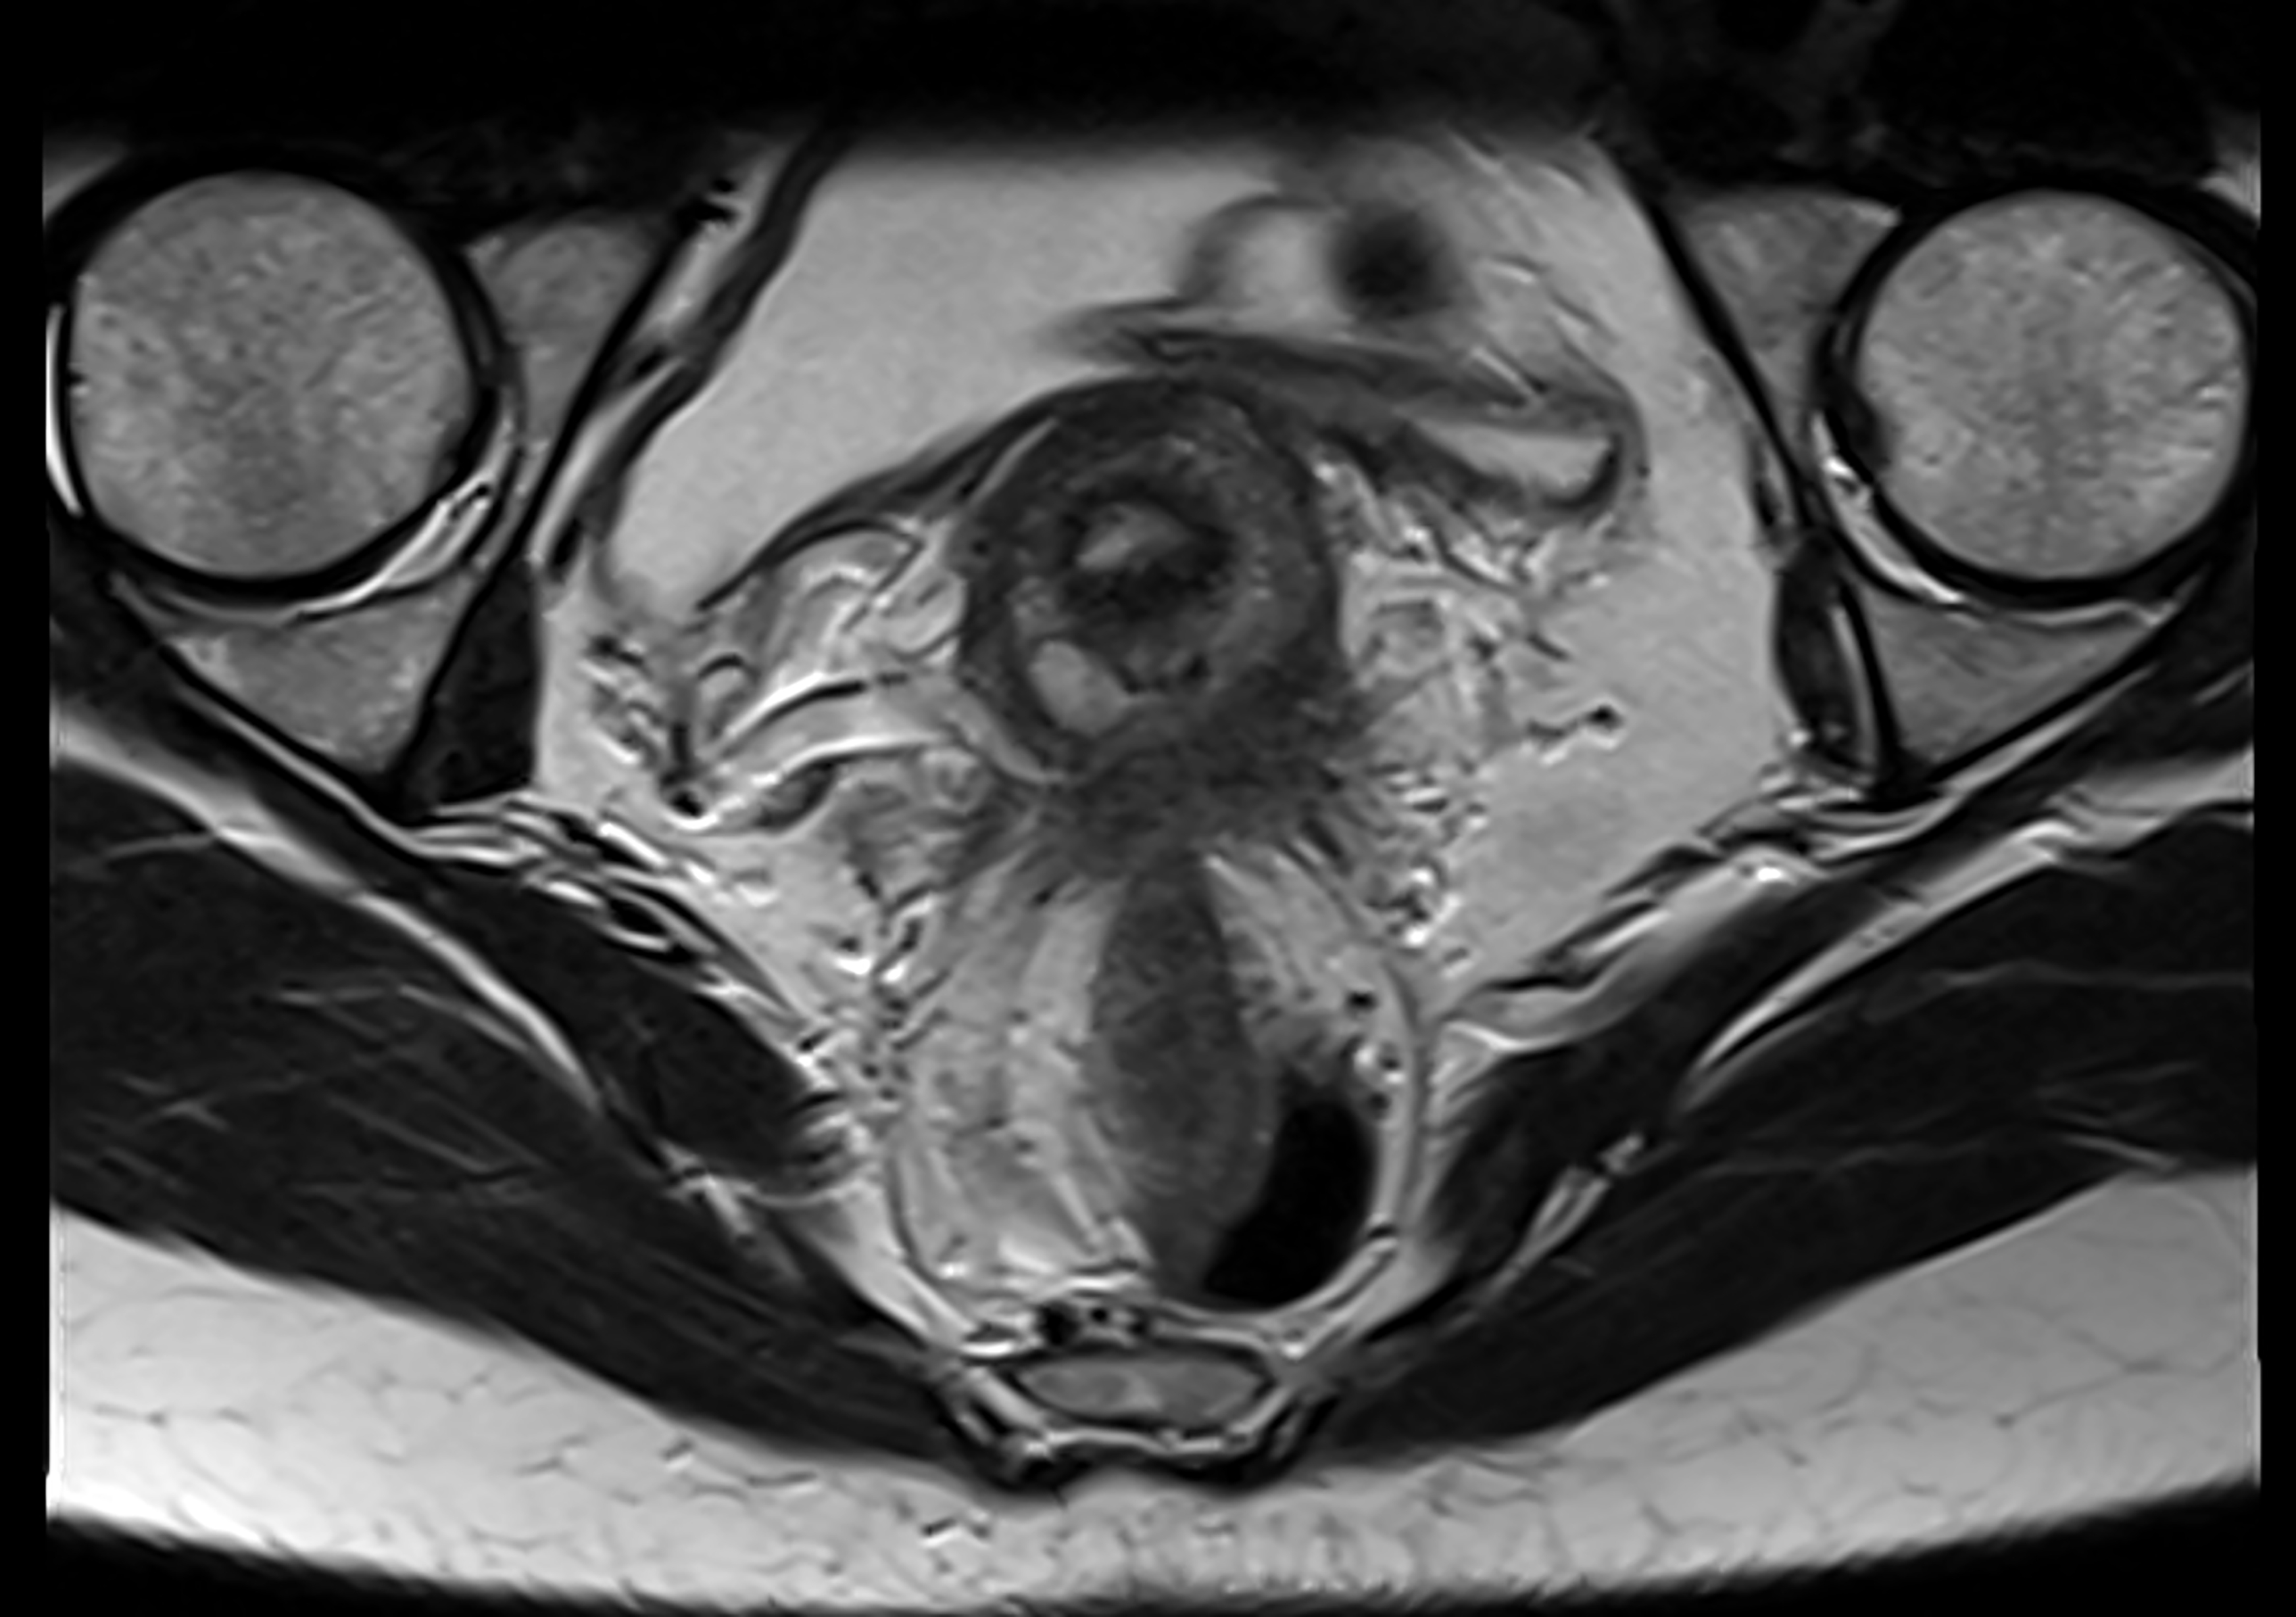

11. "Endometriosis, usually not ignored by patients, but by doctors. This goes for galore uturus-related issues."

Paul Biris / Getty Images